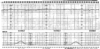

What do you see here?

- Intrapartum fetal (top) and contraction monitoring

FHR: baseline 132 bpm; moderate variability (normal: external monitoring)

1. Qualitative, not quantitative if external

2. Quantitative FHR on time: variability normal, even acceleration (going way above baseline) -

Contraction pattern: q3-4 minutes (normal)

1. Dark, vertical bars designate 1 minute so you can count how frequent the contractions are

2. #’s on vertical axis give you some basic info concerning contraction strength -> this can’t be measured via external monitor (body habitus), so internal monitoring via catheter in uterus can be used for better values